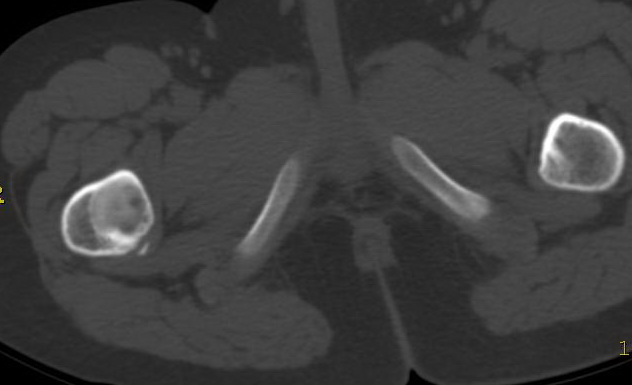

以下是引用lkc8963在2009-2-23 9:48:00的发言:[br]骨纤维性病变--非骨化性纤维瘤或局灶性骨纤首先考虑.理由:磨玻璃改变,边界清,向髓腔侧及皮质侧膨胀.最需鉴别内生软骨瘤,请楼主在轴扫上看有无点环状钙化,本例第二张图片上似见钙化,如有钙化首先考虑软骨源肿瘤.